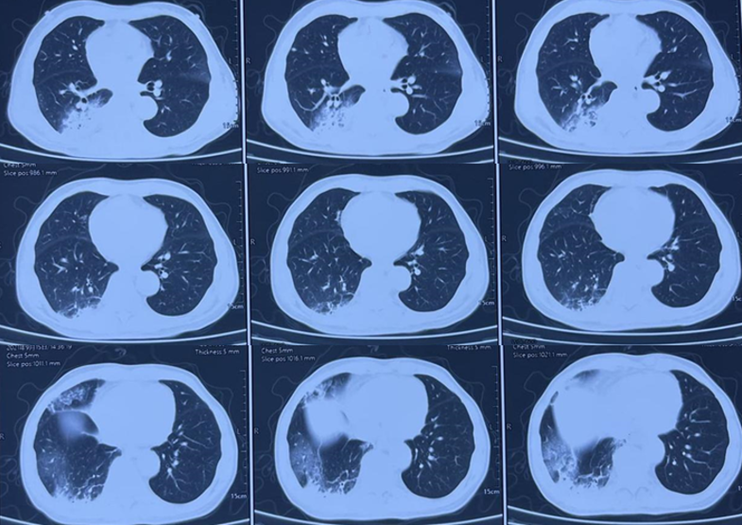

图3为AEP患者的胸部CT,可见相对较为松散的实变,另有小叶间隔增厚以及部分纤维病灶形成。患者经历了较长的诊断过程,抗感染效果不好,最终通过活检病理明确诊断。

图3  AEP患者胸部CT

图4为AFOP患者的胸部CT,表现为双肺大片实变。该患者症状较重,病情进展迅速,抗感染效果不佳,最终依靠病理诊断明确。

图4  AFOP患者胸部CT

图5为AE-IPF患者的胸部CT,表现为双肺外周带的磨玻璃影,进展迅速。

图5  AE-IPF患者胸部CT